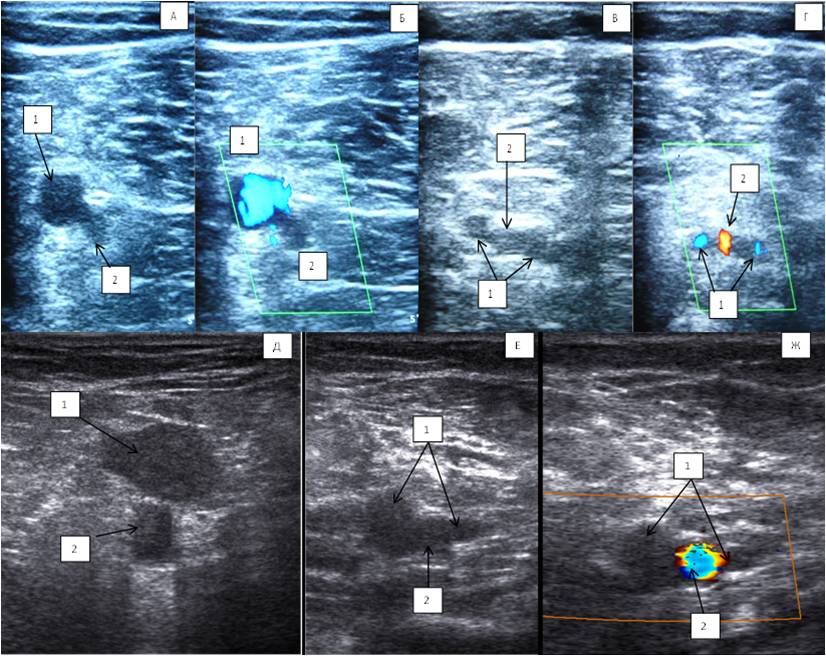

Two trunks of the PV in the distal part of the popliteal region were found in 85.7% of cases, and the vessel located medially from the PA was almost always larger than the one located laterally (Figure 5). Statistical analysis showed no statistically significant difference between the data of anatomical preparation and DS for this feature (p = 0.959).

Fig. 5. Duplex scan of the popliteal vein: (A, B, E) topography of the popliteal vein (level above the knee joint fissure); (C, D, F, G) two trunks of the popliteal vein below the knee joint cleft.

Notes: (1) Popliteal vein; (2) Popliteal artery.